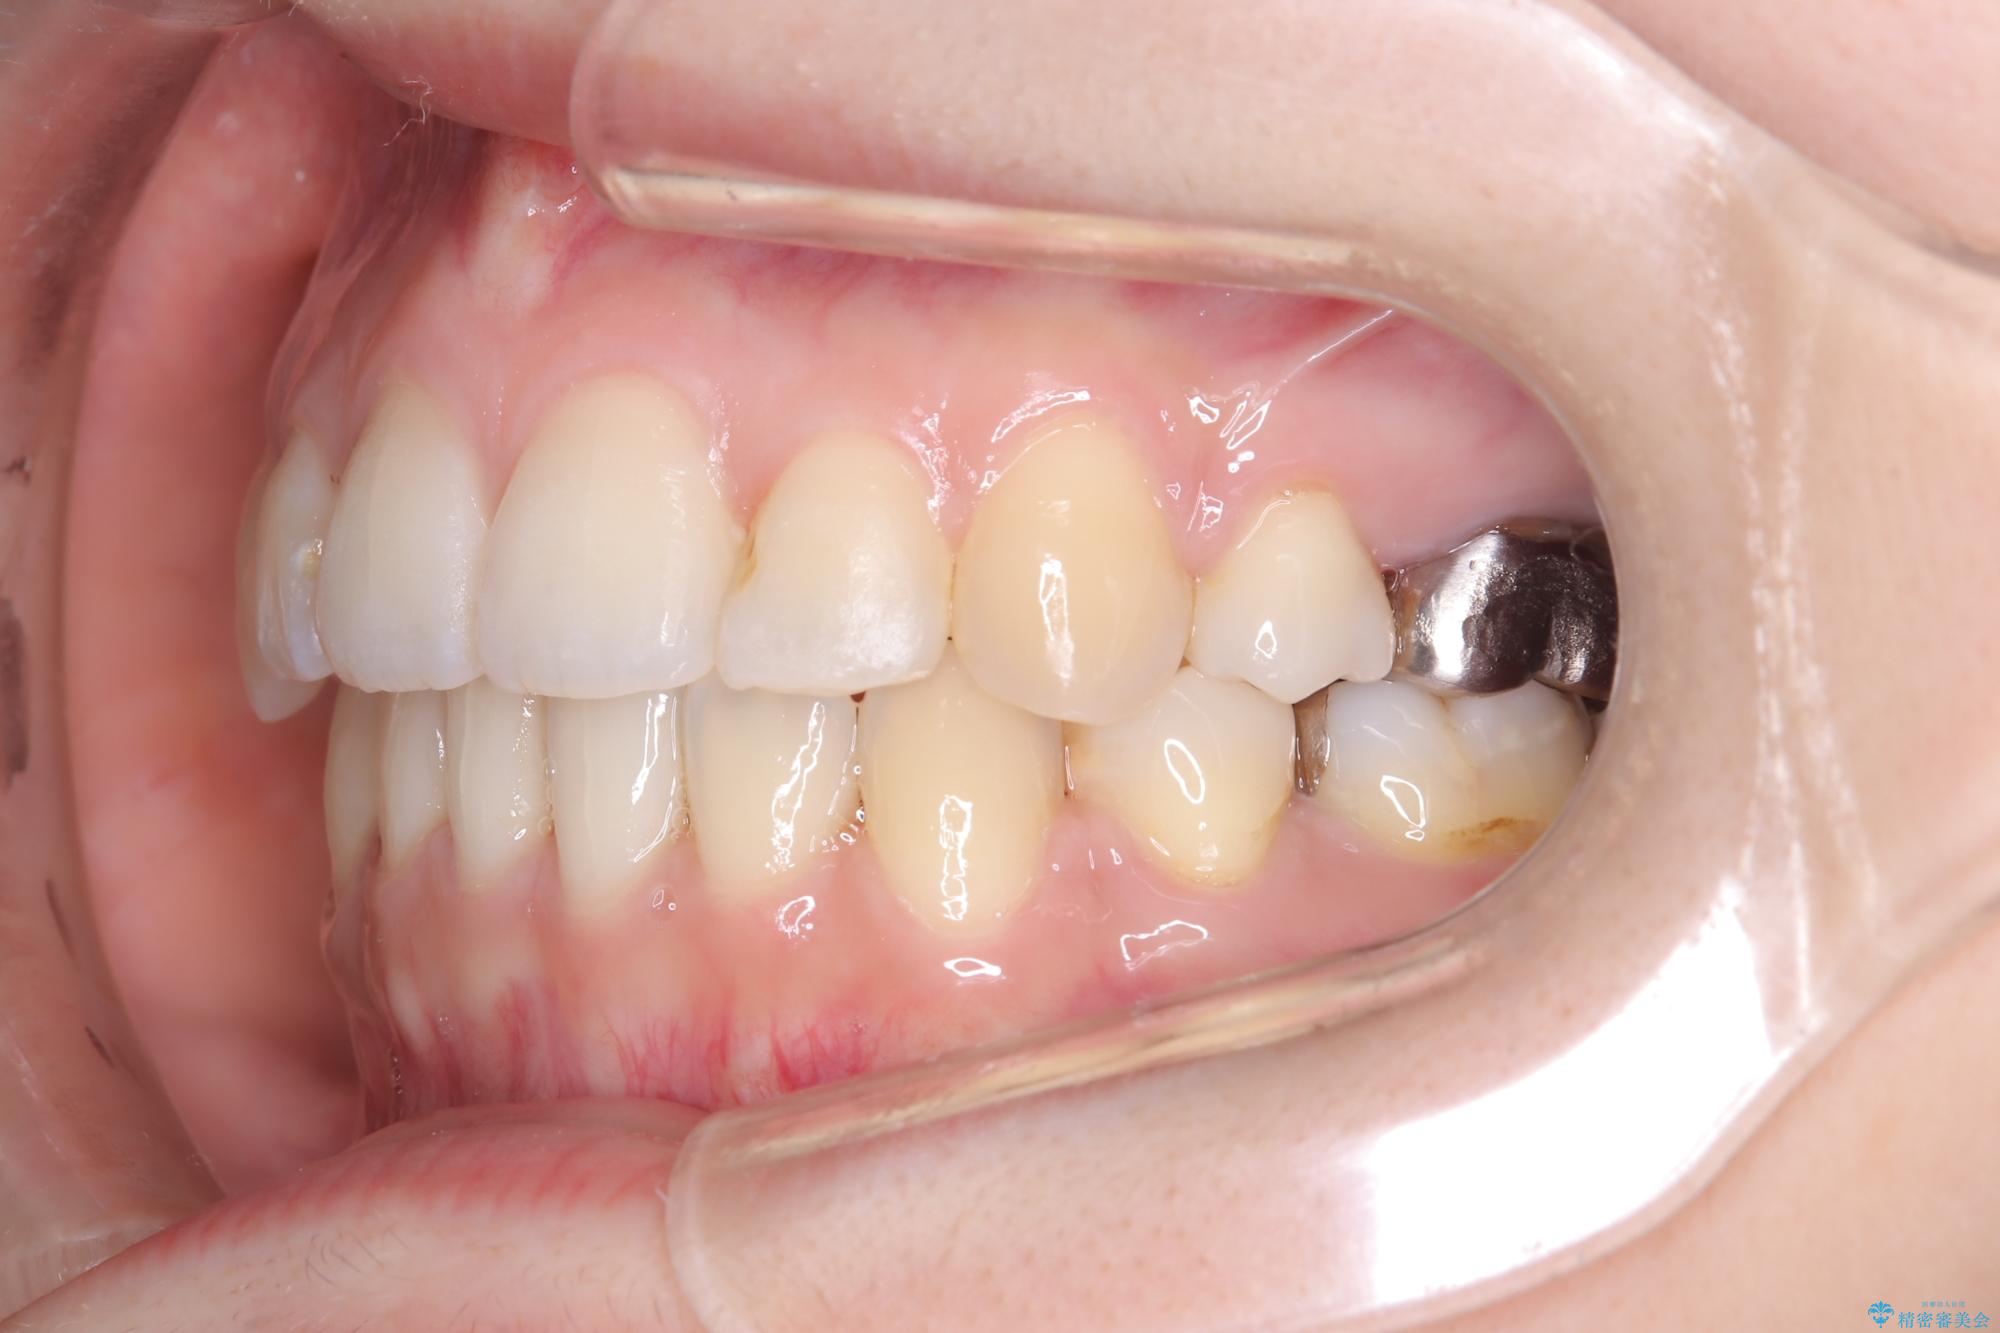

- 主訴:口元を下げて前突感を無くしたい、下の歯の凹凸も無くしたい

右側第二小臼歯、左側第一小臼歯、下顎両側第一大臼歯を抜歯しワイヤ-矯正を行いました。

骨格的顎の変位を認めたため、顔貌に対しピッタリ上下の歯の正中を合わせることは難しいと説明し、上下左右計4本小臼歯を抜歯しワイヤー矯正治療を行いました。